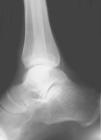

Hemos realizado tan sólo 1 caso debido a una pseudoartrosis (figs. 11 y 12), que se complicó posteriormente con una osteomielitis aguda por lo que se le realizó los 3 tiempos de Papineau. En líneas generales, la talectomía no ha demostrado buenos resultados.

Fig. 12. --Pseudoartrosis y NAV en fractura de cuello de astrágalo. Artrodesis tipo Blair

Fig. 12. --Pseudoarthrosis and avascular necrosis in a fracture of the astragalus neck. Blair-type arthrodesis.